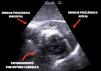

Mujer de 62 años, sin antecedentes personales, consulta por epigastralgia de cuatro días, sufriendo un ictus lacunar hemi-motor puro derecho con tomografía computarizada multimodal anodino. En el electrocardiograma se observa elevación del ST inferior con ondas Q, ingresando en la unidad de cuidados intensivos. En la ecocardiografía transtorácica se objetiva comunicación interventricular septo-basal con cara inferior aquinética, adelgazada e hiperecogénica sugestiva de pseudoaneurisma con posible ruptura miocárdica contenida (fig. 1, Video 1). Se desestima cirugía emergente ante clínica neurológica y riesgo quirúrgico por friabilidad de tejidos. A la espera de decisión final, se realiza resonancia magnética nuclear cardiaca (fig. 2), tras la que sufre parada cardiorrespiratoria en actividad eléctrica sin pulso por taponamiento con reanimación infructuosa (fig. 3, Videos 2,3). Las complicaciones mecánicas postinfarto agudo de miocardio, aunque inusuales hoy en día, siguen siendo una patología potencialmente mortal y tiempo-dependientes, donde las técnicas de imagen como la ecocardiografía siguen jugando un papel fundamental.